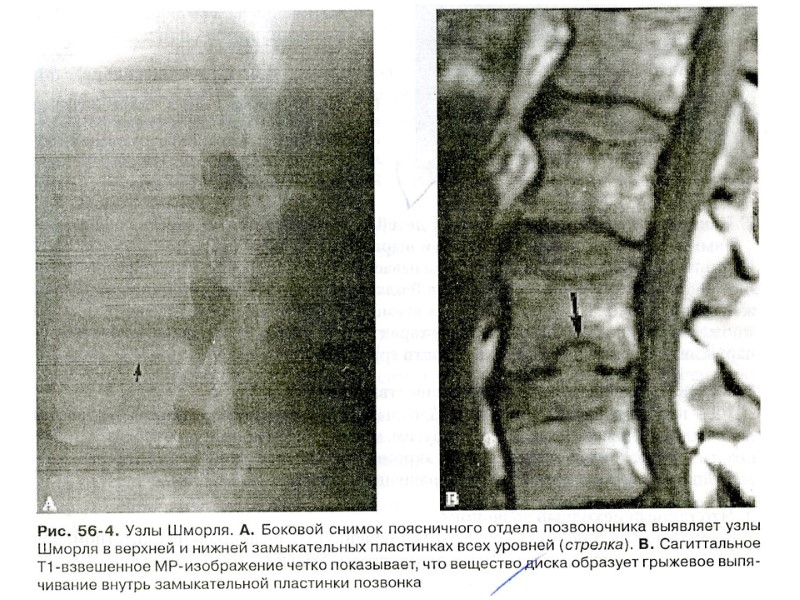

Рентгенограмма поясничного отдела позвоночника